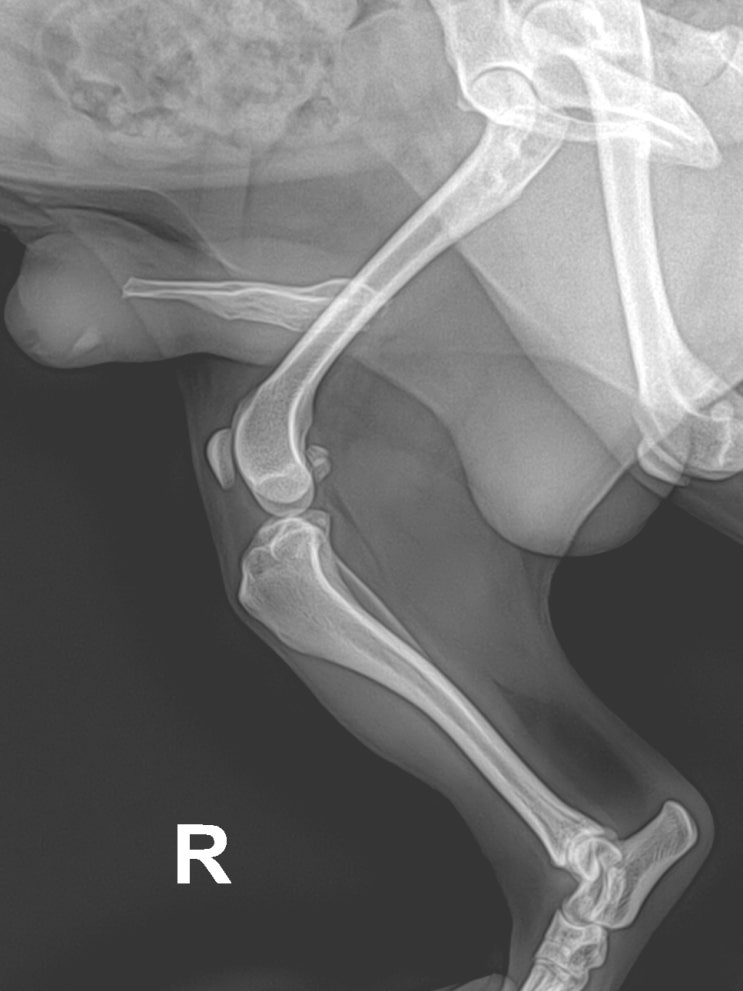

12살 시추 강아지 뒷다리 통증 원인 / 반려견 관절염 주사 치료 / 노령견 뒷다리 절뚝이는 이유 / 애완견 관절 주사 전문 동물병원 / 강아지 슬개골 탈구 내과적 치료

안녕하세요~ 굿파파 수의사입니다. 가정의 달은 너무 빠르게 지나가는 것 같네요 행복한 미소 가득한 하루 ...